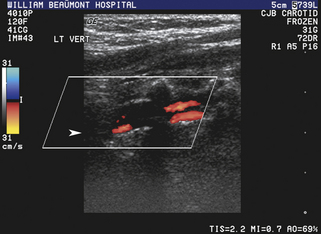

Уменьшенный поток

У пациентов с доминирующей позвоночной артерией недоминирующая, анатомически маленькая позвоночная артерия может демонстрировать характеристики кровотока с повышенным сосудистым сопротивлением со снижением скорости кровотока на пике систолы и во время диастолы. В более тяжелых случаях гипопластической, атретичной (диаметр просвета менее 2 мм) позвоночной артерии, которая может встречаться у 15% пациентов, сосудистое сопротивление по ходу сосуда может быть настолько повышено, что спектральная допплеровская волна приобретает характеристики почти полной дистальной окклюзии (т.е. отсутствие обнаруживаемого диастолического потока; рис. 11-14 ). Тяжелая обструктивная болезнь проксимальных отделов позвоночных артерий также может быть причиной снижения кровотока в вертебробазилярной системе и цереброваскулярных симптомов. В таких случаях форма волны спектральной допплеровской скорости демонстрирует форму волны tardus-parvus, характерную для затухания, форму волны с задержкой начала округлого, плохо выраженного систолического пика, плохой антеградный поток во время диастолы и значительное снижение скорости на протяжении всего сердечного цикла (рис . 11-15 ). Если в позвоночной артерии наблюдаются затухающие допплеровские сигналы, необходимо провести тщательное дуплексное ультразвуковое исследование проксимального сегмента и места расположения пораженной позвоночной артерии, чтобы определить локализацию и тяжесть любого обструктивного поражения, которое может присутствовать.

РИСУНОК 11-15. Уменьшение кровотока в средней позвоночной артерии вследствие проксимального стеноза. Кривая скорости имеет классическую форму tardus-parvus с округлым, плохо выраженным систолическим пиком и снижением скорости на протяжении всего сердечного цикла. (Пиковая систолическая скорость [ПСВ] составляет 13 см/сек.)